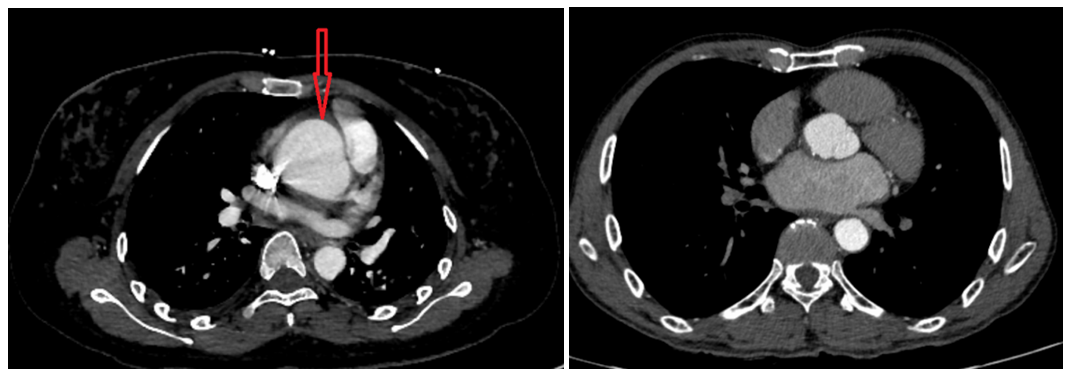

箭头所示即主动脉破口

妊娠合并主动脉夹层在临床上非常罕见,单纯主动脉夹层的死亡率极高,妊娠合并主动脉夹层,在发病的首个24小时内,死亡率可达50%以上,并随着时间的延长进一步增加。小蕾的情况如果不及时处理,主动脉就会进入“炸弹随时引爆”的状态,一旦发生爆炸,血液从主动脉破口涌入胸腔,造成大出血,失去救治机会。

一定要做好孕前检查,注意孕期血压,特别是在怀孕中后期,妊娠高血压发病率升高,如控制不好将直接增加主动脉夹层的发病风险。孕妇夹层风险更高,一定要尽早手术,替换病变血管,才能尽早挽救孕妇及胎儿生命。